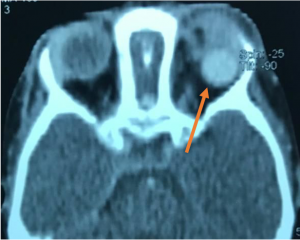

USG Doppler – shows increased velocity with reversal of blood flow direction, dilated Superior Ophthalmic Vein (SOV) and arterial pulsations.

CT/MRI - proptosis, EOM enlargement, dilated and tortuous SOV, with engorgement and early enhancement of the ipsilateral cavernous sinus. CT Angiography- differentiate direct and indirect CCF but cerebral angiography is used for accurate diagnosis and intervention. |

Traumatic carotid-cavernous fistula) Axial T2WI MRI of right orbit showing dilated superior ophthalmic vein along its whole course (orange arrow) b) Coronal T2WI MRI showing dilated superior ophthalmic vein (white dotted arrow) with engorgement of the extra ocular muscles compared to the contralateral normal side (orange arrows) |